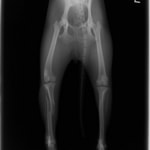

症例:交通事故による椎体脱臼

柴犬:9歳、避妊雌

交通事故直後、胸腰部に激しい疼痛、両後肢に完全麻痺を認め、シェフシェリントン徴候を呈していました。レントゲン検査において、第11-12胸椎間の脱臼が認められました。

脊髄の減圧、脊柱管の再構築・安定化を目的に、片側椎弓切除術およびMatrixMANDIBLE Plateによる椎体固定を実施しました。

隣接椎体を架橋するようにプレートを設置しました。

術後レントゲン写真